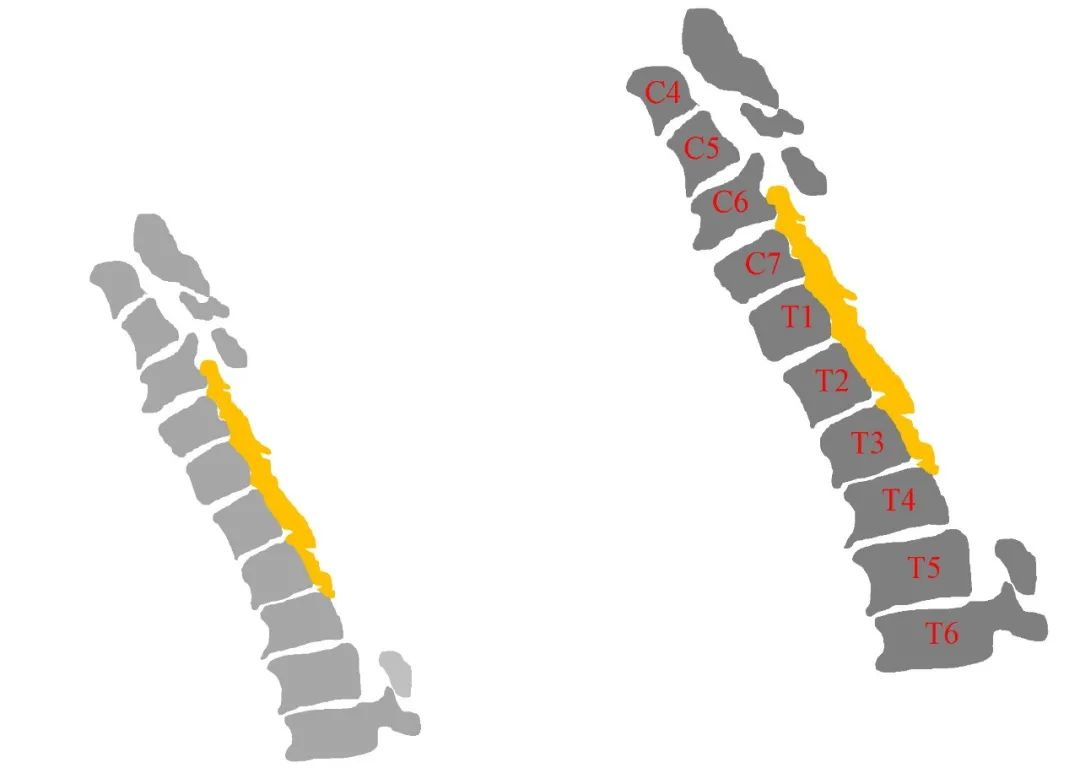

病史:M, 34 y/o

Numbness of right lower limb for 2 months, weakness for 1 week

Urination disorder

Body Weight: 120Kg; BMI: 39.5

影像资料:

Thoracic spinal stenosis(T2-T3)

Thoracic spinal stenosis decompression(T2-T3)